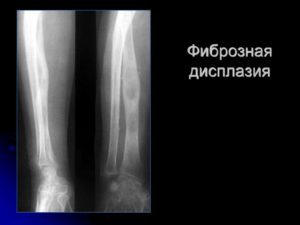

- Рентгенологическая картина фиброзной дисплазии разнообразна.

- Патологические участки могут быть то более плотными, то более прозрачными по сравнению с окружающей костью, иногда имеют вид «матового стекла».

- Одни очаги четко отграничены зоной склероза, контуры других расплывчатые, что особенно характерно для костей черепа.

- Нередко выявляются узуры в кортикальном слое, а при наличии перелома — отчетливая периостальная реакция.

- затемнение по типу матового стекла: 56% [1]

- очаг однородный склеротический: 23%

- очаг кистозный: 21%

- очаг с четко определенными границами

- расширение костей с интактными вышележащими костями